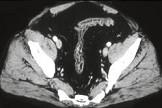

问题 男,41岁,腹痛、腹泻、腹胀、脓血便、里急后重、疲乏无力,结合图像,选择最可诊断 ( )

选项 A.溃疡性结肠炎 B.结肠克罗恩病 C.结肠结核 D.假膜性肠炎 E.结肠淋巴瘤

答案 A